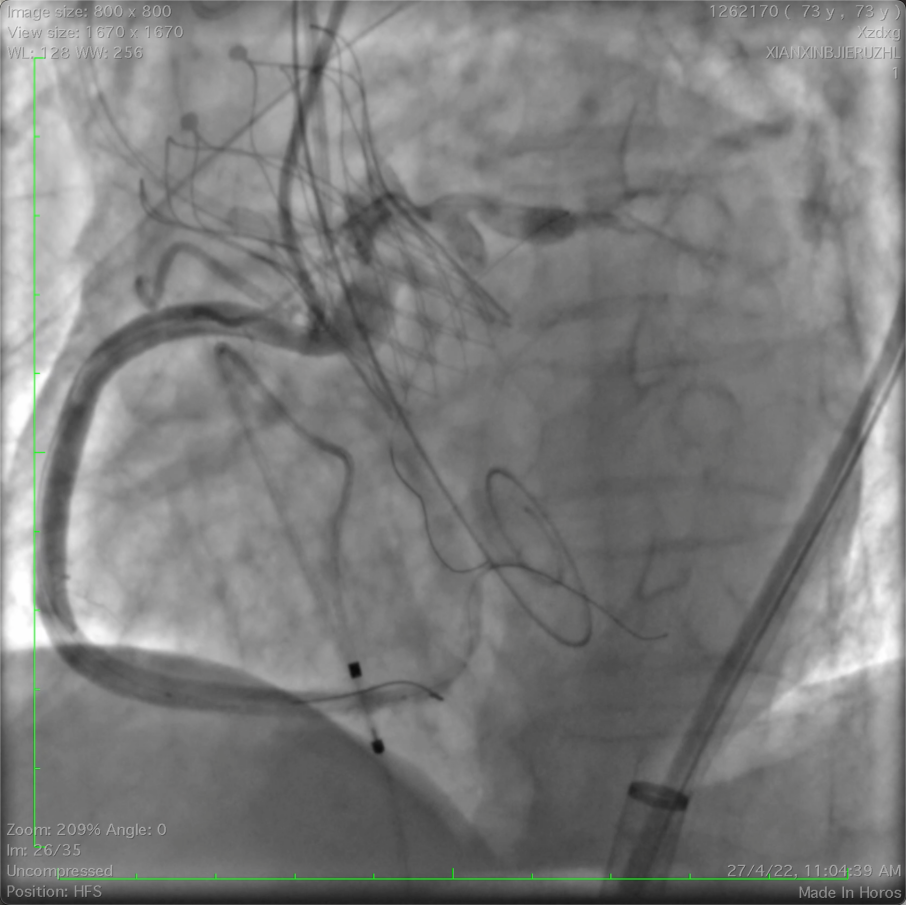

球囊预扩

图片

双侧冠脉显影,

18mm球囊几乎封堵瓣口,无明显反流。

冠脉保护下释放瓣膜

左冠口疑似遮挡

IVUS检查冠脉开口,

进一步精准评估冠脉开口遮挡情况